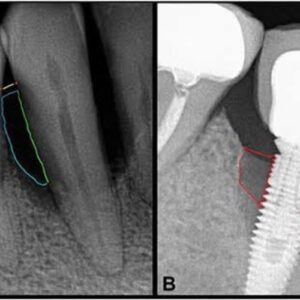

d) Periodontitis also known as peri-implantitis:

Peri- implantitis is the infection caused by bacteria and food lodgement that accumulate around the gums where implants are placed. Peri-implantitis is one of the major reasons why dental implants fail. It means bone around the implant has started to resorb which may lead to implant failure.